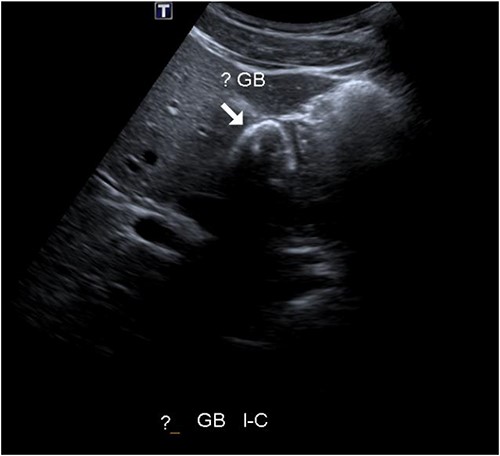

A 25-year-old man presented to the hospital with 1-day history of right upper abdominal pain with a similar episode a week prior. He was otherwise fit and healthy with no other medical or surgical history. In the emergency department, he was haemodynamically normal, and he had right upper quadrant abdominal tenderness. His blood tests show normal inflammatory markers and normal liver function tests (LFTs). He had an ultrasound of the upper abdomen, which reported a difficult visualization of the gallbladder that was nearly completely contracted around calcific stones. There was no definite wall hyperaemia but appears thickened, and probe tenderness was present (see Fig. 1). He was diagnosed with acute on chronic cholecystitis and antibiotics were commenced. Symptoms improved so he was subsequently discharged with plan for an elective laparoscopic cholecystectomy in the next 2 weeks.

Abdominal ultrasound showing potential contracted gallbladder.